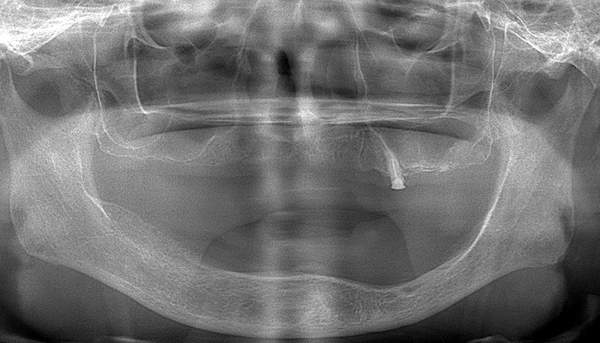

3.レントゲン診査

レントゲンで、顎の骨の厚みや、顎の関節の状態と位置を見ていきます。また、噛む力は強いのかなども診ることができます。 歯があれば、その状態も診査していきます。

治療内容 レントゲンをみて最低限の長さのインプラントを右上の奥歯の位置に埋入しました。インプラントと骨の結合(オッセオインテグレーション)と歯肉の治癒を待ち、アバットメントをいれて型取りをして、入れ歯を作成しました。極力薄くするために、金属をもちいた入れ歯にしました。